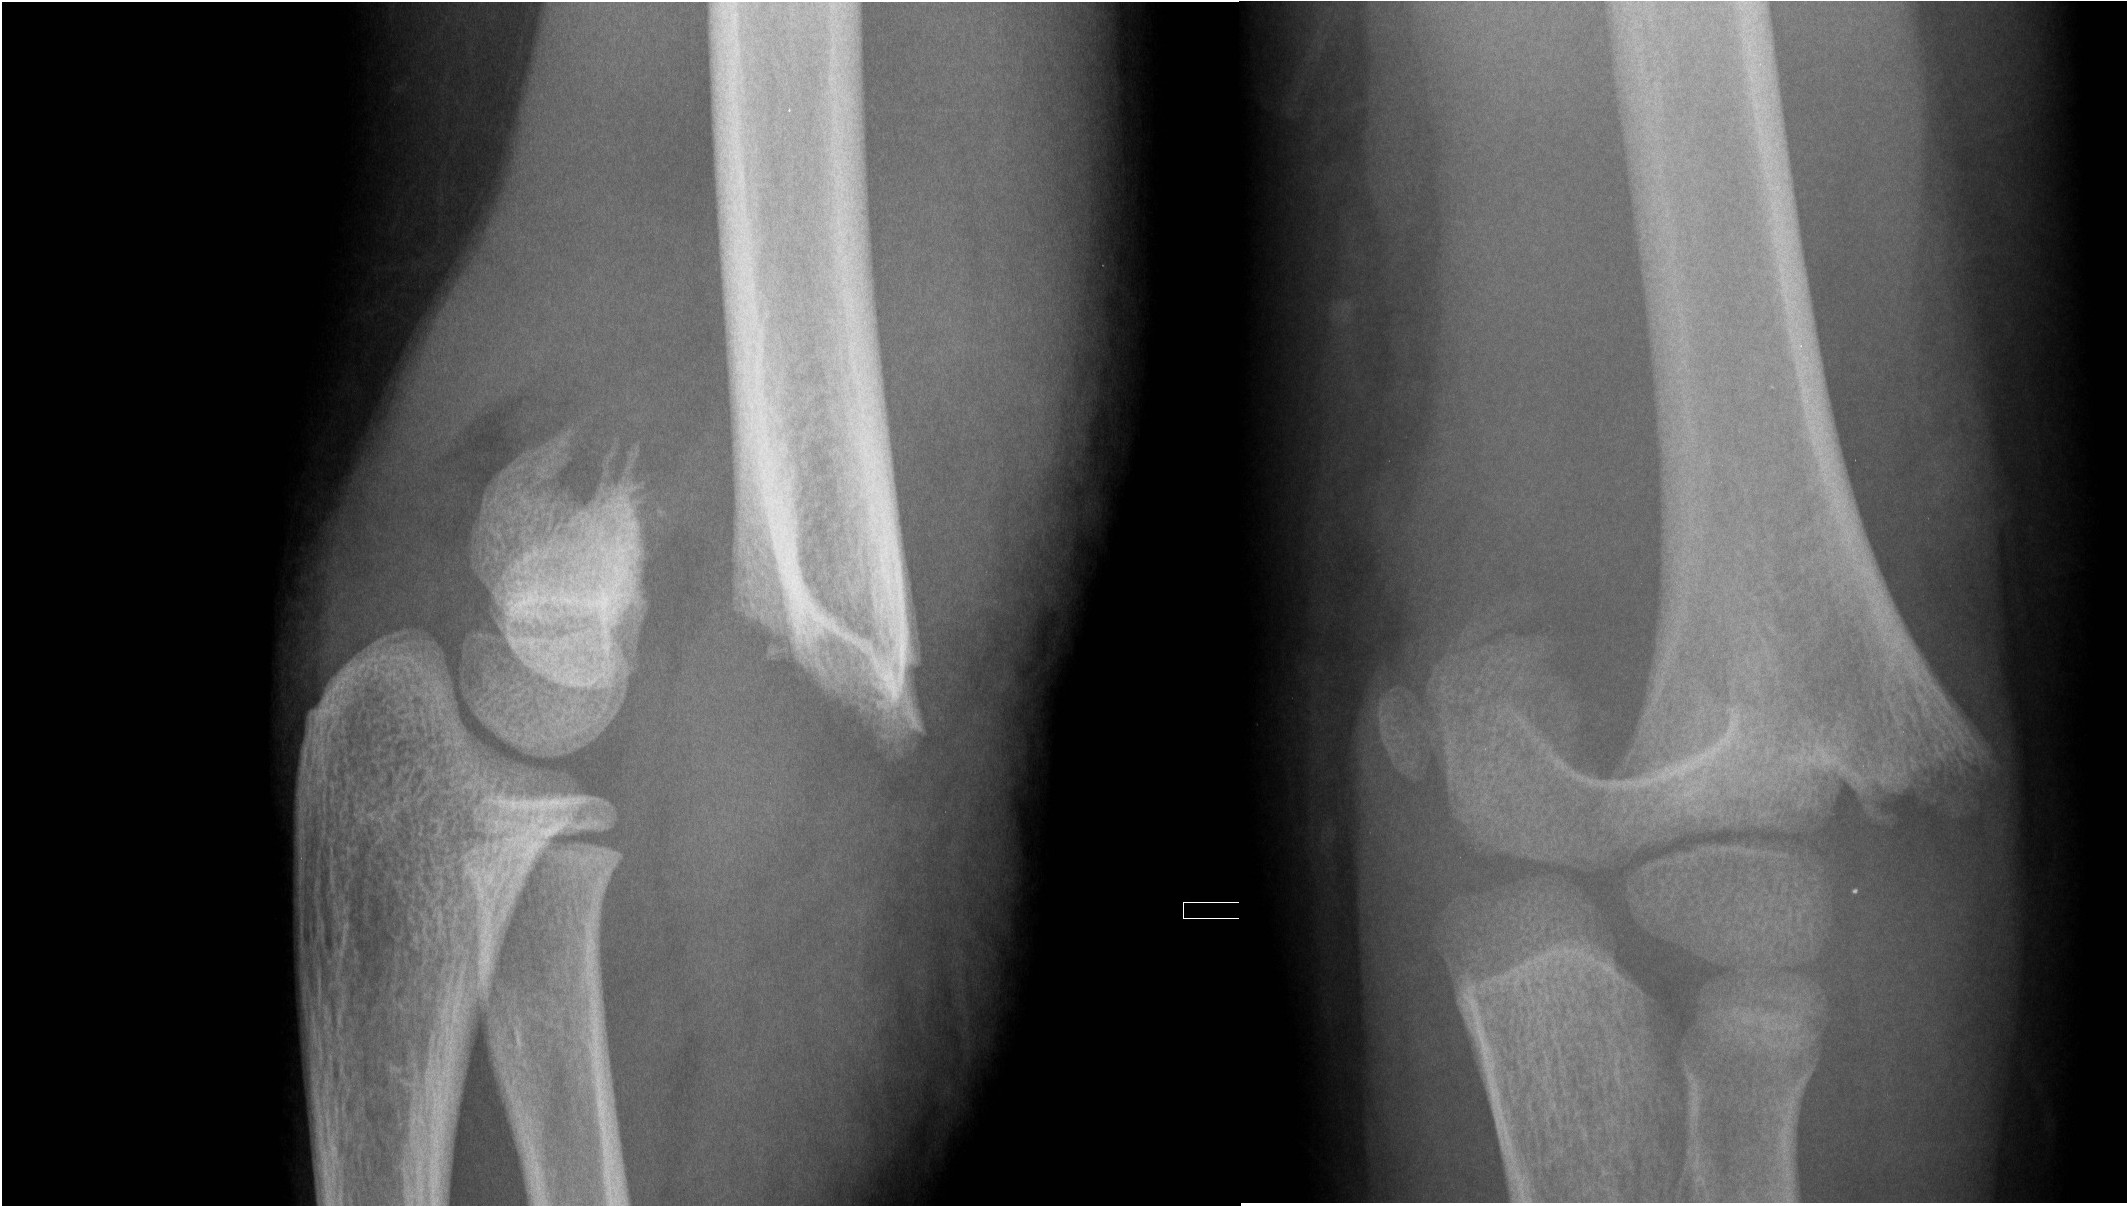

Medial Epicondyle Fractures

- Medial epicondyle fractures are often missed because they are mistaken as an ossification centre. Assess ulnar nerve function in any medial epicondyle fracture.

Undisplaced medial epicondyle fractures

- Above elbow plaster backslab at 90 degrees flexion with follow up in Orthopaedic Fracture clinic in 7-10 days.

Displaced medial epicondyle fractures

- Discuss with the Orthopaedic team for further management.

Displaced medial epicondyle

Lateral condyle fractures

- All lateral condyle fractures should be discussed with the Orthopaedic team for further management. They are generally unstable and prone to displacement and often require operative fixation.

Lateral condyle fracture